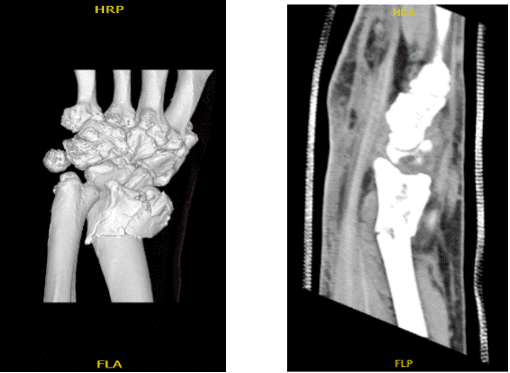

An MRI was reviewed and discussed by the doctor; a comminuted distal radial fracture is present with intra-articular extension where displacement measures up to 3 mm. Ulnar angulation is also present. Degenerative changes are present at triscaphe and first carpometacarpal joints.

The fracture was comminuted in more than three parts with intraarticular extension. The fracture was reduced manually and then fixed with multiple K-wires and checked under fluoroscopy. Finding it in an acceptable position, a volar plate was put and fixed with the use of ball-tipped K-wires.

The picture was then again taken to confirm the good reduction. The plate was fixed to the fracture with the use of locking and nonlocking screws. One Screw was wasted. to pull the distal fragment with the plate also. Pictures were taken in between and then the final picture was taken and saved. They were found to be in an acceptable position.

After two weeks the patient was seen in the office for his post operative visits, with x-rays of his left wrist. It showed that the surgical plate and screws traverse an incompletely healed oblique fracture of the distal left radius. Hardware appears intact.